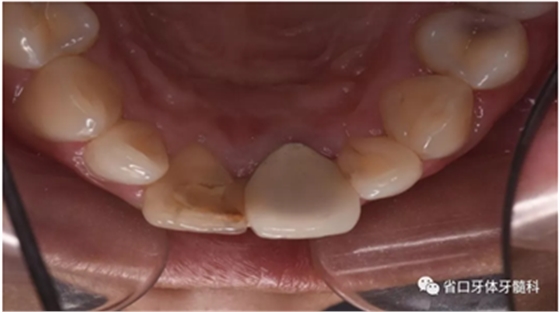

口腔檢查:口腔衛(wèi)生狀況一般,11牙冠變色,近中鄰面見齒色填充物,舌側窩內(nèi)見白色充填物,邊緣見黑色齲壞物,近中探及懸突,叩痛(土),松(—),冷診無反應;21烤瓷全冠修復,烤瓷冠顏色未知,唇側齦緣發(fā)黑,叩痛(土),松(—)。圖1/2

圖1 治療前患牙唇側觀

圖2 治療前患牙舌側觀